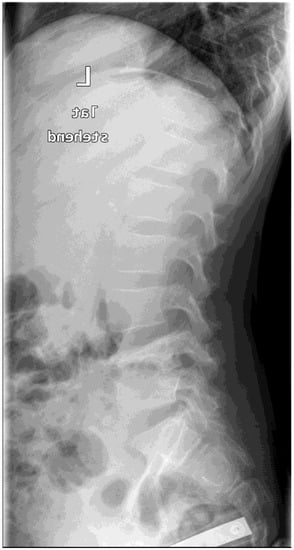

Different methods of imaging were initiated before detecting the final diagnosis of PSD: five children received a sonography of the hips and four patients an X-ray image (Figure 1) while in two cases a CT was performed. The final diagnosis was made by MR-imaging in all cases (Figure 2).

4.5. Imaging

For musculoskeletal pain, the gold standard is plain radiography in two planes as the first imaging method [15]. Thus, the adequate diagnostic tool (MRI of the spine) was not considered immediately. This may be attributed to the pain which was often (50%) located outside of the spine region. Furthermore, a MRI is elaborate to perform as the children often require sedation or anesthesia. Typical MRI alterations are a reduced disc height, disc hypointensity on T1-weighted images, and disc hyperintensity on T2-weighted images. The involved disc shows fluidlike signal intensity in T1- and T2-weighted MRI images.

Figure 2. MRI scan (sagittal view) of the lumbar spine (Pat. No. 10).